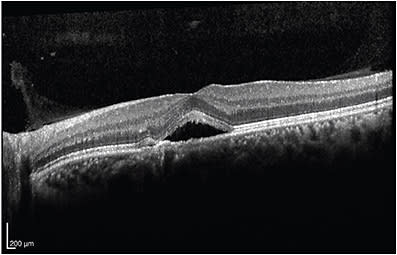

A 47-year-old male physician presented initially with a 2-week history of metamorphopsia in the left eye. After 6 months of observation, which did show some initial improvement in central subfield thickness and volume, the improvement stalled despite stress reduction and a 1-month trial of eplenerone. At month 6, progressive retinal pigment epithelium (RPE) atrophy was noted (Figure 1), and the decision was made to undergo half fluence photodynamic therapy with verteporfin. An area of 2800 µm was treated (total area of RPE changes) with 15 mg of verteporfin.